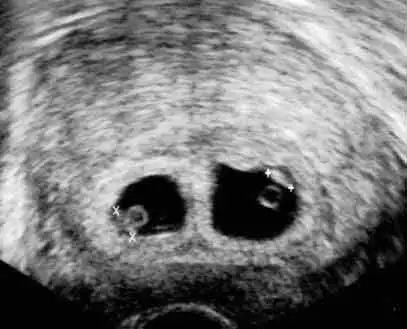

Valla google a ikiz gebelik 5 hafta yazdım çıkan sonuç bu 🥹 Baya benziyor.

Eki Görüntüle 3370656

Bi ara bi 4+6 gibi bişey dedi ama tam anlayamadım zaten o anın stresi ve heyecanıyla algılarım kapandı hep 🥲🥲 ama şey dedi son adet tarihiyle hamilelik uyumlu dedi sıkıntı yok dedi ☺️ muayenem de bi tuhaftı. Karından ultrasonda göremedi, kese gözükmüyor diyince zaten başımdan kaynar sular döküldü. Vajinal bakalım dedi onda da baya kurcaladı etti gördü keseyi ama işte ortasında bölme var, ya ikiz ya başka bi durum, değişik bilmiyorum ya 😔 kan da verdim betaya bakacaklar. Gidince kalp atışı mevzusunu sorucam bakalım